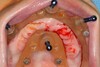

La fausse gencive rose en céramique permet de recréer la gencive naturelle au maxillaire.

Le passage des brossettes est prévu entre chaque pilier.